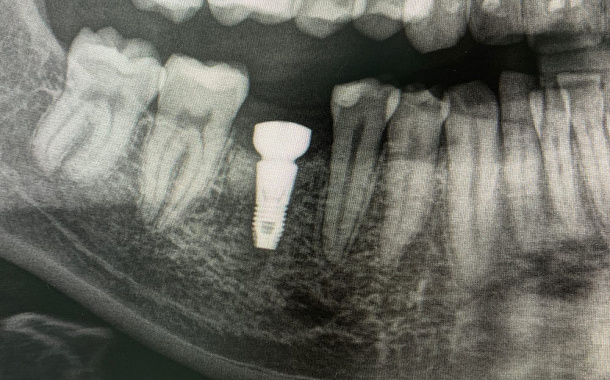

Применение Indiba после стоматологических процедур, таких как удаление зубов, костная пластика и имплантация, обеспечивает ряд значительных преимуществ:

- Улучшение приживаемости имплантатов: усиление кровоснабжения в области имплантации способствует лучшей интеграции имплантата с костной тканью.

- Исследование, опубликованное в Journal of Clinical Medicine (2020), показало, что применение Indiba после имплантации зубов ускоряет процесс остеоинтеграции на 30-40%.